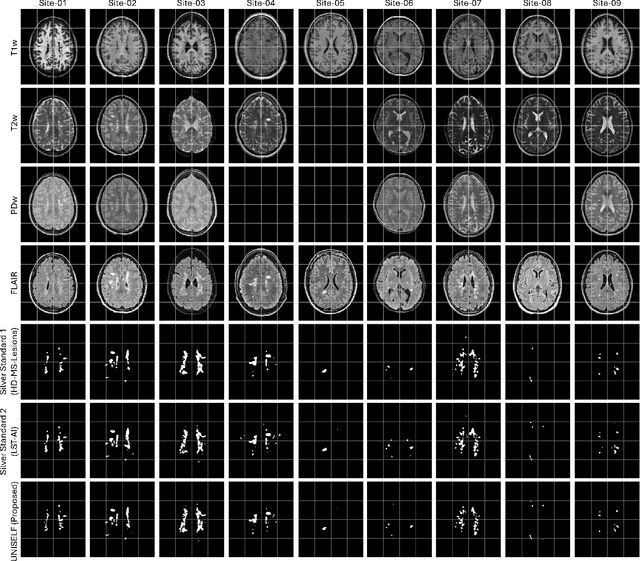

Abstract:Automated segmentation of multiple sclerosis (MS) lesions using multicontrast magnetic resonance (MR) images improves efficiency and reproducibility compared to manual delineation, with deep learning (DL) methods achieving state-of-the-art performance. However, these DL-based methods have yet to simultaneously optimize in-domain accuracy and out-of-domain generalization when trained on a single source with limited data, or their performance has been unsatisfactory. To fill this gap, we propose a method called UNISELF, which achieves high accuracy within a single training domain while demonstrating strong generalizability across multiple out-of-domain test datasets. UNISELF employs a novel test-time self-ensembled lesion fusion to improve segmentation accuracy, and leverages test-time instance normalization (TTIN) of latent features to address domain shifts and missing input contrasts. Trained on the ISBI 2015 longitudinal MS segmentation challenge training dataset, UNISELF ranks among the best-performing methods on the challenge test dataset. Additionally, UNISELF outperforms all benchmark methods trained on the same ISBI training data across diverse out-of-domain test datasets with domain shifts and missing contrasts, including the public MICCAI 2016 and UMCL datasets, as well as a private multisite dataset. These test datasets exhibit domain shifts and/or missing contrasts caused by variations in acquisition protocols, scanner types, and imaging artifacts arising from imperfect acquisition. Our code is available at https://github.com/uponacceptance.